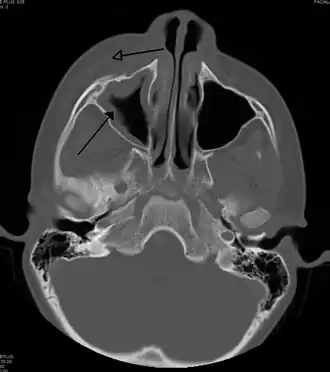

-

MRI image showing sinusitis. Edema and mucosal thickening appear in both maxillary sinuses. -

Maxillary sinusitis caused by a dental infection associated with periorbital cellulitis -

Imaging by either X-ray, CT, or MRI is generally not recommended unless complications develop.[66] Pain caused by sinusitis is sometimes confused for pain caused by pulpitis (toothache) of the maxillary teeth, and vice versa. Classically, the increased pain when tilting the head forwards separates sinusitis from pulpitis.[68]

For cases of maxillary sinusitis, limited field CBCT imaging, as compared to periapical radiographs, improves the ability to detect the teeth as the sources for sinusitis. A coronal CT picture may also be useful.[60]